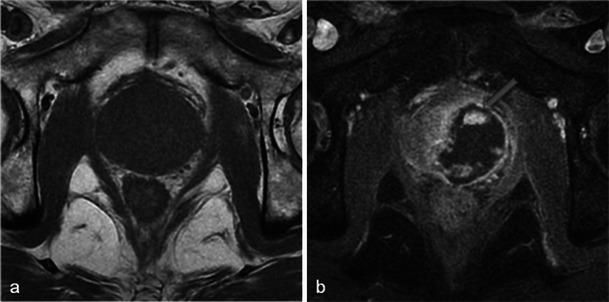

In this technique, a photosensitising agent is introduced intravenously, then activated by local laser illumination to induce tumour necrosis. Treatment efficacy is assessed by magnetic resonance imaging (MRI).

We illustrate specific post-treatment MRI aspects at early and late follow-up with pathological correlations.

• Dynamic phototherapy is a new and promising focal therapy for prostate cancer. • One-week MRI shows increased volume of the treated lobe and large, homogeneous necrosis area. • Six-month MRI shows significant changes of the prostate shape and signal. • Six-month MRI becomes "base line" appearance for further follow-up or monitoring.

在该技术中,将一种光敏剂静脉注射,然后通过局部激光照射激活以诱导肿瘤坏死。通过磁共振成像(MRI)评估治疗效果。

我们阐述了早期和晚期随访时特定的治疗后MRI表现及其与病理的相关性。

• 动态光动力疗法是一种用于前列腺癌的新型且有前景的局部治疗方法。• 一周后的MRI显示治疗叶体积增大以及大片均匀的坏死区域。• 六个月后的MRI显示前列腺形态和信号有显著变化。• 六个月后的MRI成为进一步随访或监测的“基线”表现。